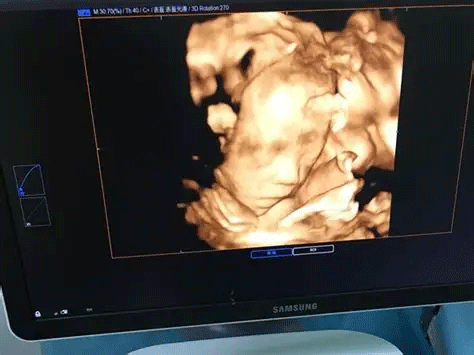

三维彩超,即彩色多普勒超声检查的一种,检查图像呈土黄色,通过多普勒超声仪器发出超声波,对体内各项器官进行成像。三维即其图像是立体的,可以更直观的看到器官的形态,及时发现病变并进行治疗。三维彩超常用于产检,用来判断胎儿的生长发育的情况或是否出现畸形等。

2、清晰度不同

目前临床上维彩超检查是直接对胎宝宝先天头面部畸形的判断,可以拍到宝宝生长发育的局部立体图像。而四维相对于三维来说,会更清晰,对胎宝宝畸形,如唇腭裂、四肢发育畸形、脑膜膨出、脊柱裂、腹壁裂和心血管畸形等能够做早期诊断,并且能够立体显示胎宝宝的颜色、各器官的发育情况,甚至在母体内吸吮、睡觉等动态也可以捕捉到。。

三维和四维并不是彩色图片,只是和黑白色有差异,二者呈现的都是土黄色的画面。但三维的成像是静态的,是一张图片,而四维彩超则是动态的,像一张动图一样,并且有的医院会允许刻成光盘带回家收藏起来。